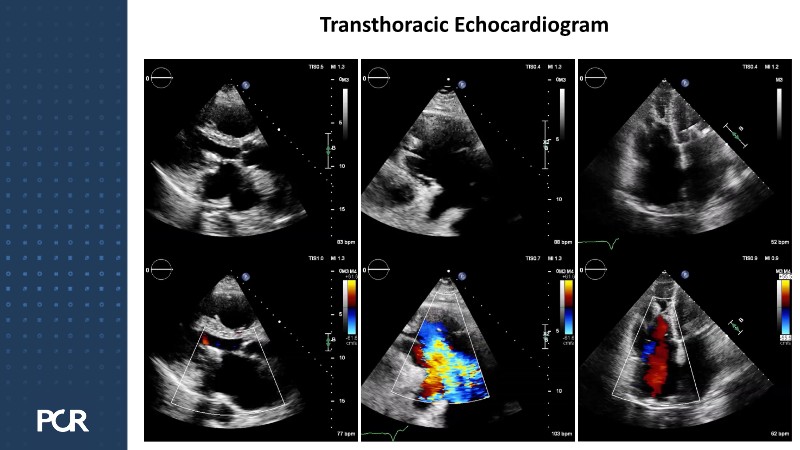

This interventional session explores therapeutic strategies for mitral and tricuspid regurgitation, focusing on the clinical decision-making process between repair and replacement. Through two clinical cases, a 78-year-old male patient with severe degenerative mitral regurgitation and an 88-year-old female patient with atrial functional mitral regurgitation, experts review available transcatheter options and their procedural integration. The session features a presentation of several innovative devices, including the PASCAL Precision system, the EVOQUE system, and the SAPIEN M3 platform, highlighting their role in contemporary valve interventions.